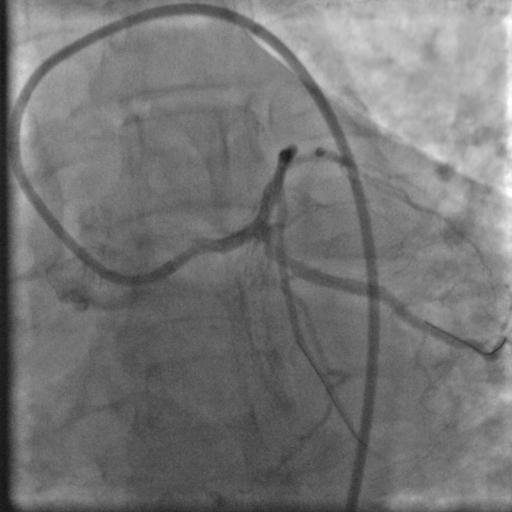

Başka merkezde CTO işlemine alınıp başarısız olup kliniğimize başvuran hastaya RCA uzun ve tandem CTO lezyonları özel mikro kateter ve teller ile geçilerek balon ve stent işlemleri başarıyla sonuçlandı.